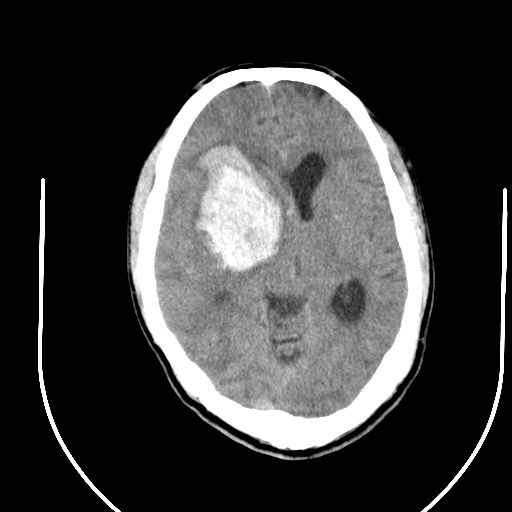

右侧基底节区脑出血并破溃入脑室。

1右侧基底节脑出血伴脑干出血并破入脑室系统脑疝形成2梗阻性脑积水

1)右侧基底节脑出血伴脑干出血并破入脑室系统。2)大脑镰下疝。3)梗阻性脑积水。

1、右侧基底节脑出血伴脑干出血并破入脑室系统。

2、大脑镰下疝。

3、梗阻性脑积水。